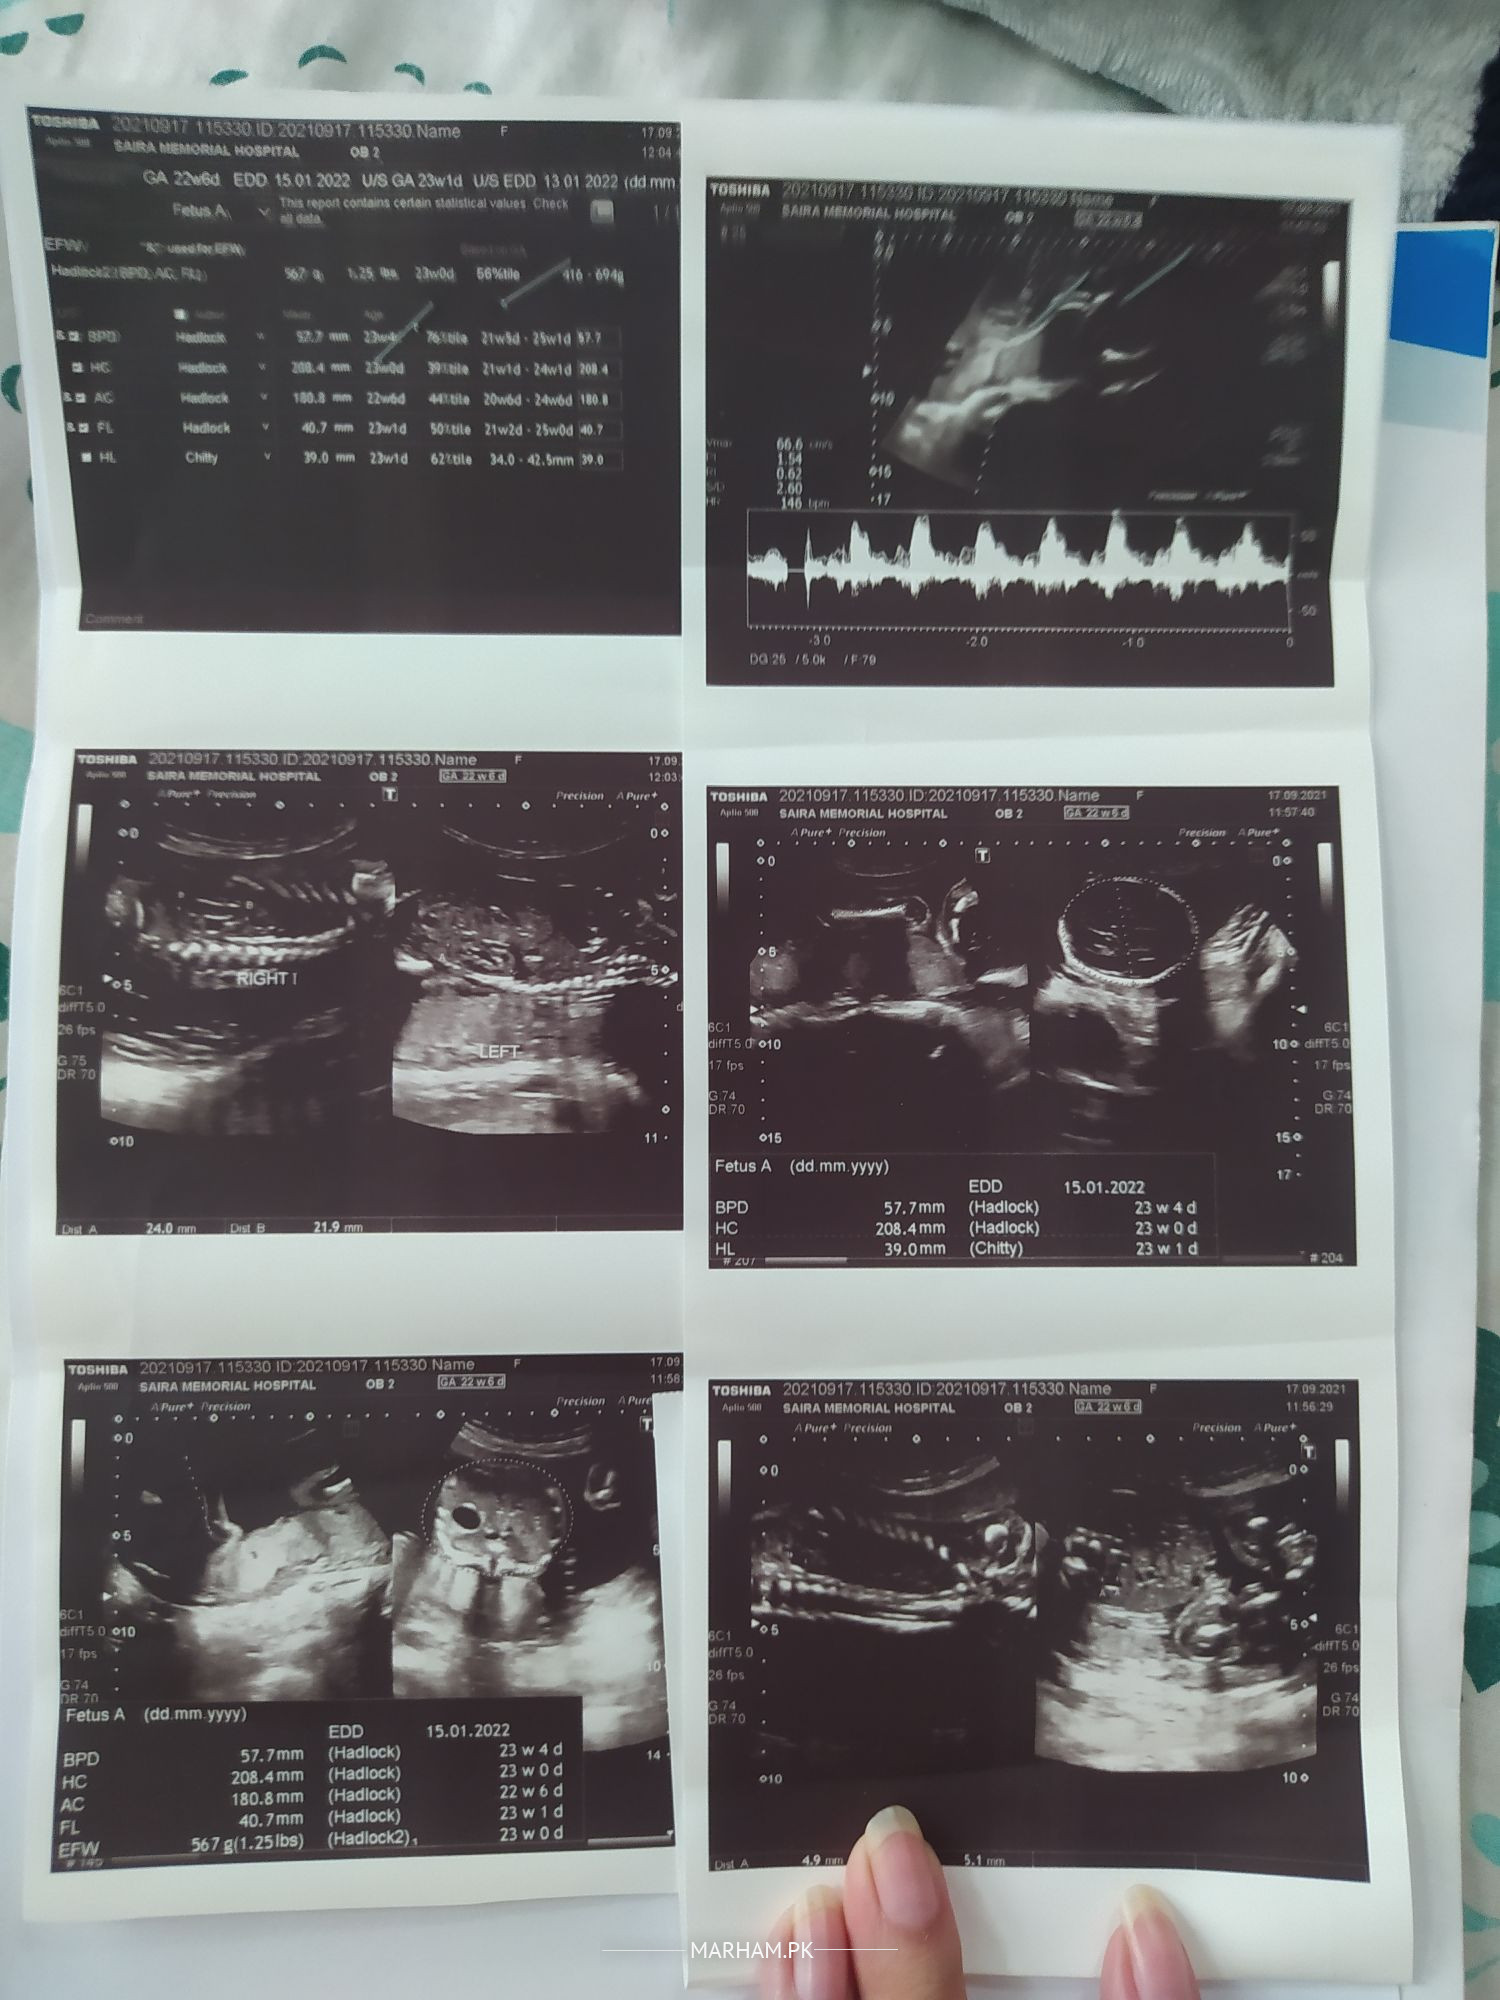

i had my anomaly scan at 20th week, which shows mildly prominent pelvicalyceal system of both kidneys measuring 4.5mm. i repeated the scan at 22nd week and the problem is still there and have increased a bit (4.9mm). Please let me know if it is something to be worried about.